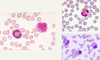

Tissue from a raven; what is the etiology?

Poxvirus